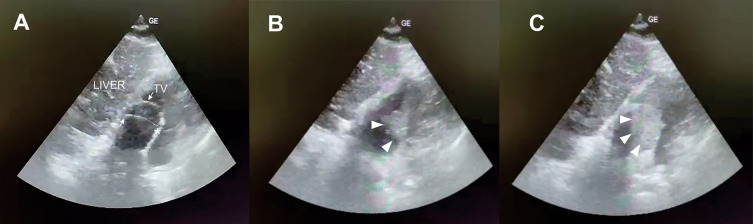

Guidewire loss is a rare complication of central venous catheterization. A 65-year-old male was hospitalized in a high-dependency unit for exacerbation of chronic obstructive pulmonary disease, pneumonia, erythrocytosis, and clinical signs of heart failure. Upon admission, after an unsuccessful right jugular approach, a left jugular central venous catheter was placed. The next day, chest radiography revealed the catheter located in the left parasternal region, with suspected retention of the guidewire, visually confirmed by the presence of its proximal end inside the catheter. The left parasternal location of the catheter and the typical projection of the guidewire in the coronary sinus, later confirmed by echocardiography, raised suspicion of a persistent left superior vena cava (PLSVC). Agitated saline injected into the left antecubital vein confirmed bubble entry from the coronary sinus into the right atrium. After clamping the guidewire, the catheter was carefully retrieved along with the guidewire without any complications. This is the first reported case of guidewire retention in PLSVC and coronary sinus. It underscores the potential causes of guidewire loss and advocates preventive measures to avoid this potentially fatal complication.